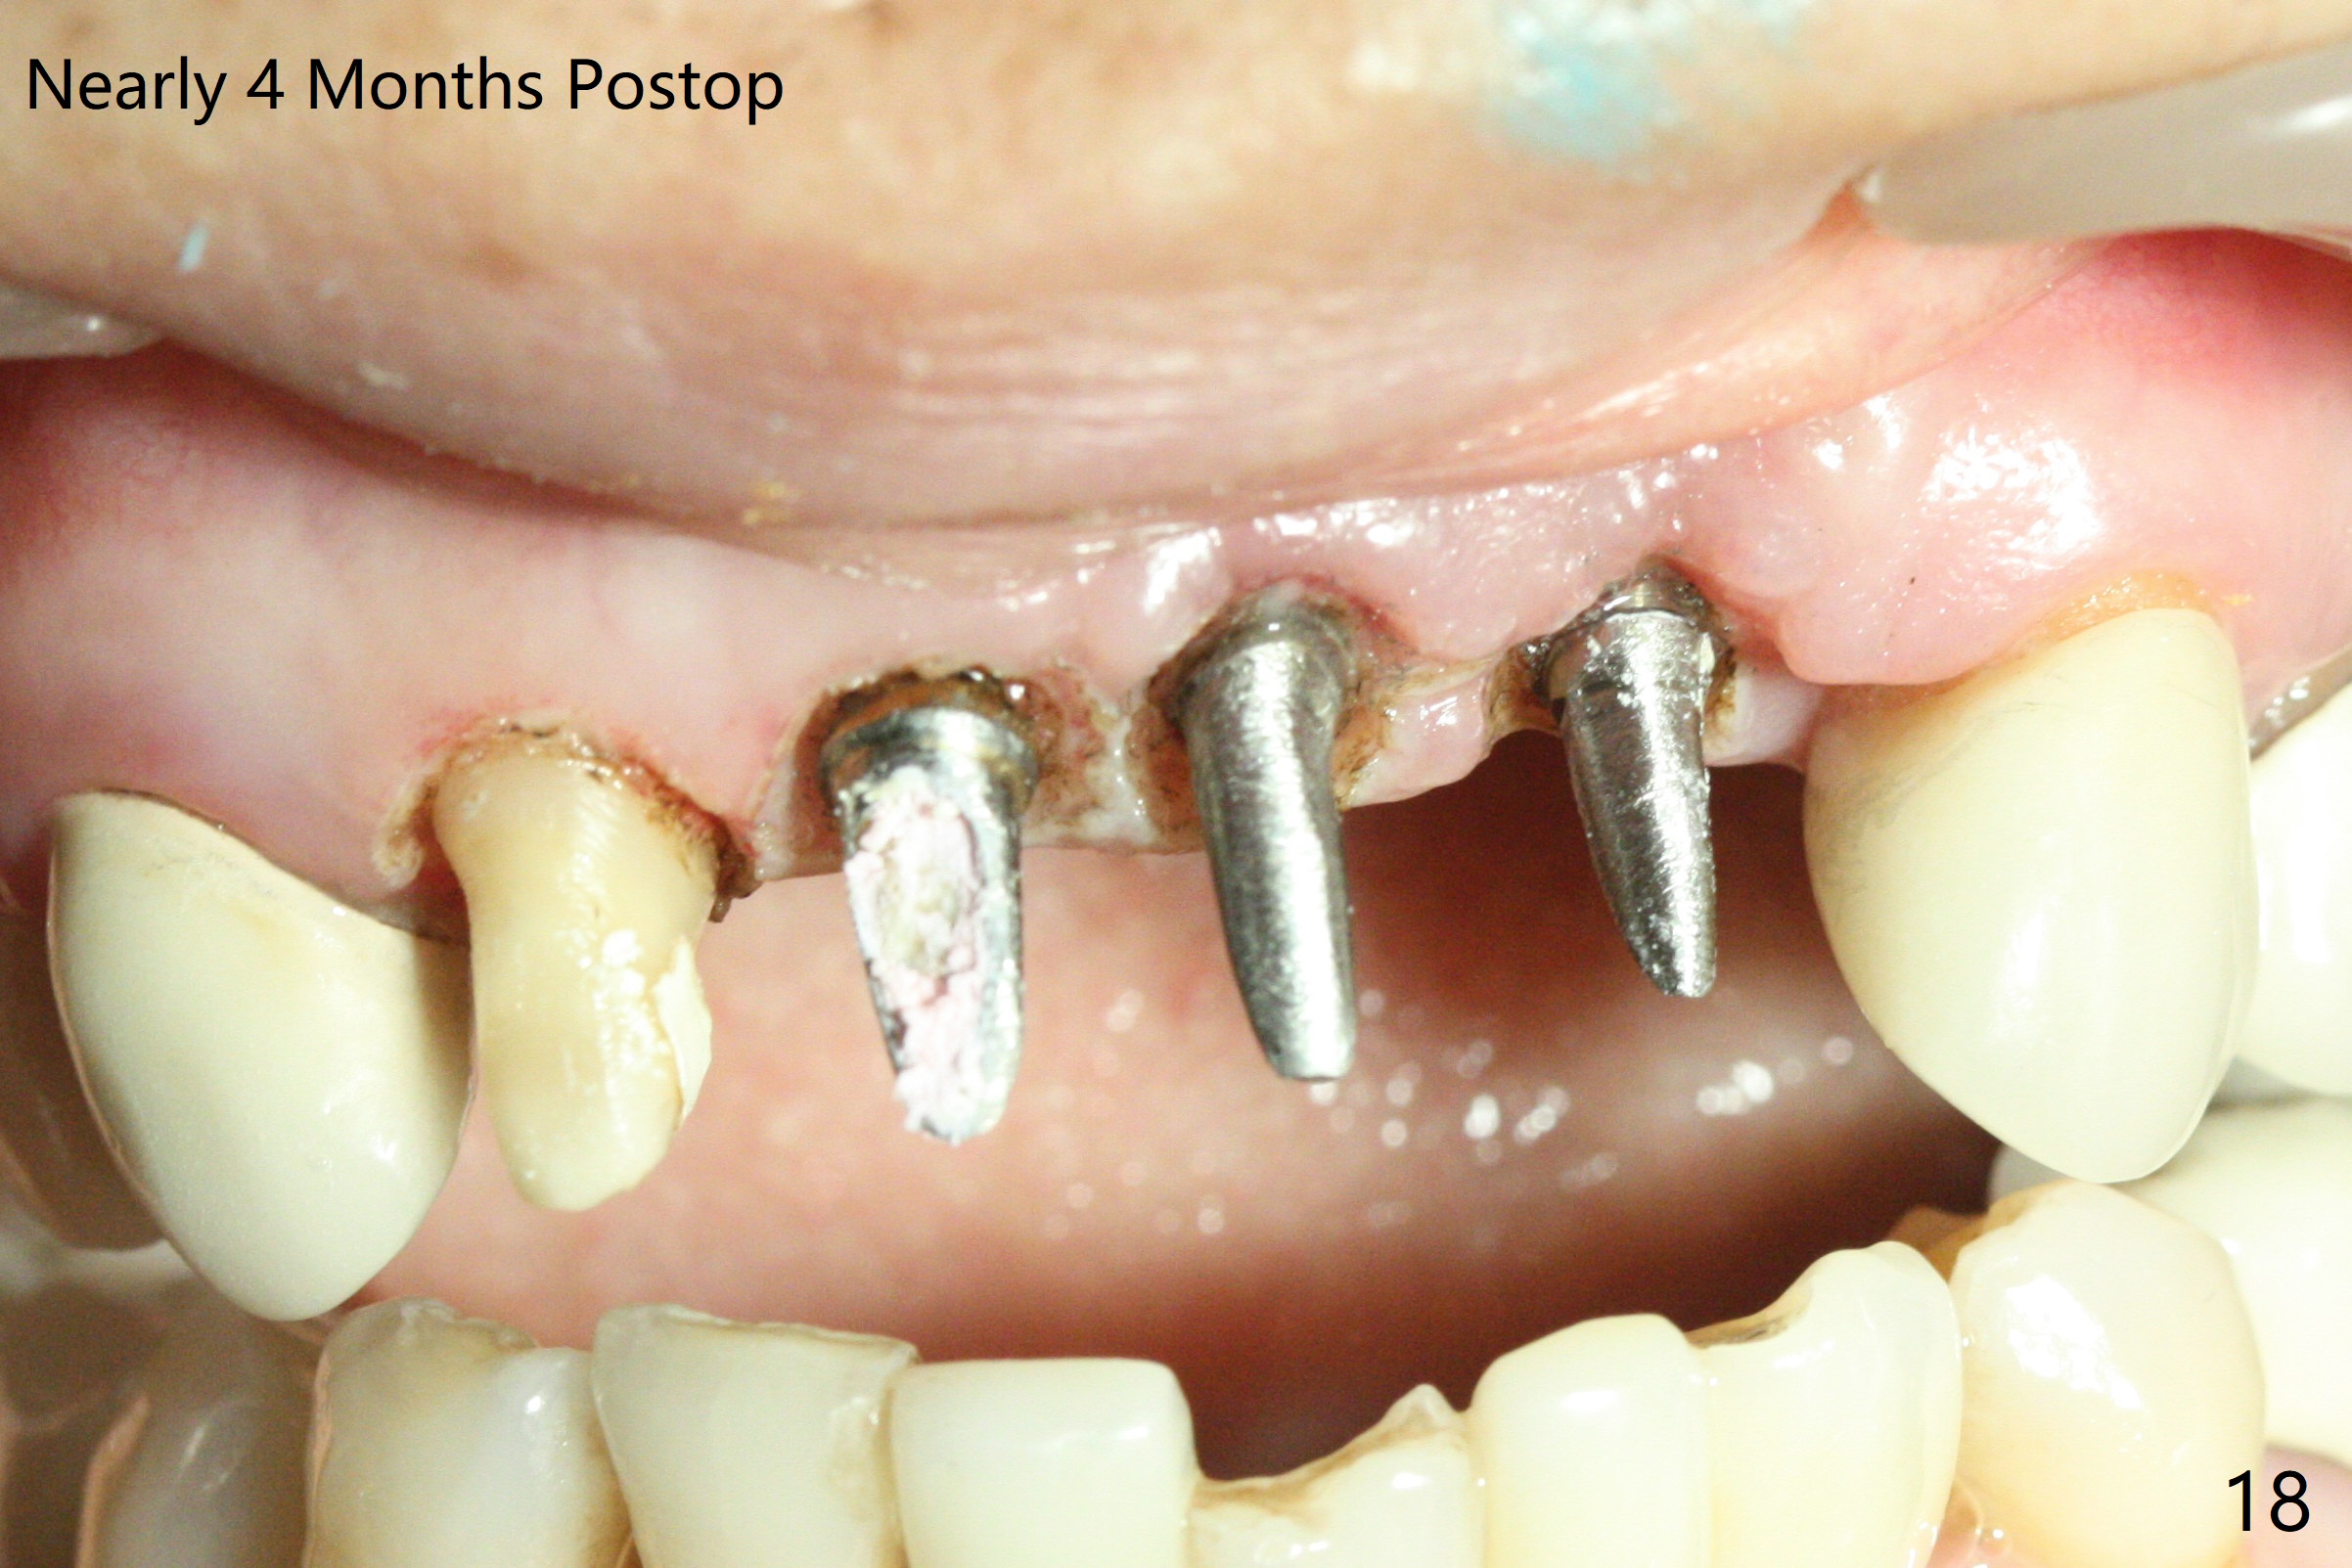

M

Incision shows exposure of microthreads at #9 and major threads at #10 due to buccal placement (Fig.1). There is bone palatal to the implant at #10 (Fig.2 P), to which a new implant will move. After implant removal, a narrower 1-piece implant (2.5x14(4) mm) is placed palatally at #10 (Fig.3,4) in combination of guide and free hand. At the site of #9 after implant removal, the guide is not used; a 3x17 mm angled 1-piece implant is placed with bad trajectory (Fig.5,6). After re-adjustment (Fig.7), the implant is placed at the right orientation (Fig.8). It appears that the guide is helpful. Allograft is placed mainly buccally (Fig.9,10 *), followed by a piece of collagen membrane (Fig.11). After tension release, flaps are approximated (Fig.12). The buccal gingiva at #9 and 10 recede nearly 2 months postop (Fig.13). Less recession at #9 is associated with more inflammation (Fig.14). The margin of the provisional is adjusted for gingival margin down growth and easy self cleaning with Water Pik (Fig.15). One month later, the gingival inflammation reduces, while there is no obvious buccal collapse (Fig.16,17). Impression is taken after laser gingivectomy nearly 4 months postop (Fig.18). While the gingiva around the implant at #9 is inflamed (periimplantitis?), the gingival cuff at #10 is well formed 5.5 months postop immediately before cementation (Fig.19). The buccal concavity at #10 is minimal (Fig.20). The gingival inflammation at #9 will be hopefully resolved after cementation of the final restorations (Fig.21). There appears to be new bone formation around the coronal implant threads 5.5 months postop (immediately post cementation, Fig.22). The microthreads at #9 may be not covered by the bone, the reason for the gingival erythema. The redness at #10 is asymptomatic 5.5 months post cementation (Fig.23). 粘固后两年牙槽嵴骨质并没有再生(图二十四),说明第一术中植体必须植入骨下(基台部分要长,否则难于修复),第二牙槽嵴处不应该有压力,植入2.5毫米植体,最后钻头应该是2.5毫米,骨下1-3毫米(尝试项目)。